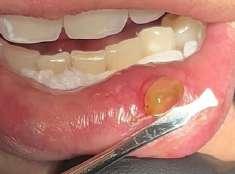

Il mucocele del cavo orale è la seconda lesione più comune. Nella fascia di età compresa tra 10 e 29 anni, il tasso di incidenza è più elevato. Il mucocele è caratterizzato da un accumulo di mucine. Ha una forma a cupola. Di solito hanno un colore bluastro. Il

mucocele si trova più comunemente sul labbro inferiore, seguito dalla mucosa buccale e dal pavimento della bocca. L'incisione tradizionale con bisturi e/o l'escissione chirurgica, la marsupializzazione, la micromarsupializzazione, l'iniezione di corticosteroidi, l'agente sclerosante, la criochirurgia, l'elettrochirurgia e il laser sono tutte procedure validate per il trattamento del mucocele in letteratura.

I laser a diodi forniscono una guarigione delle ferite e un tasso di recupero più rapidi rispetto ai loro rivali. Grazie alle sue

qualità antibatteriche e antinfiammatorie, questa terapia laser ha l'ulteriore vantaggio di migliorare la guarigione delle ferite senza infezioni o edema.

Le procedure laser-assistite sui tessuti molli presentano i vantaggi di un minimo sanguinamento intraoperatorio, edema e dolore postoperatorio, oltre a tempi chirurgici, cicatrici e coagulazione minimi.

Questo caso è coerente con precedenti segnalazioni di escissione del mucocele utilizzando un laser a diodi.

L'enorme quantità di tessuto rimosso e il livello di comfort del paziente supportano ulteriormente il fatto innovativo che può essere utilizzato anche per il mucocele di grandi dimensioni.

I mucoceli della mucosa orale sono malattie tumorali benigne delle ghiandole salivari minori della mucosa orale. Si verificano più comunemente nella mucosa labiale. Possono essere causate da una rottura dell'epitelio della ghiandola che secerne saliva nello spazio extraghiandolare e forma una pseudocisti (mucoceli da stravaso) oppure da un blocco del flusso salivare dovuto ad una proliferazione epiteliale del dotto escretore che forma una cisti salivare (cisti da ritenzione).